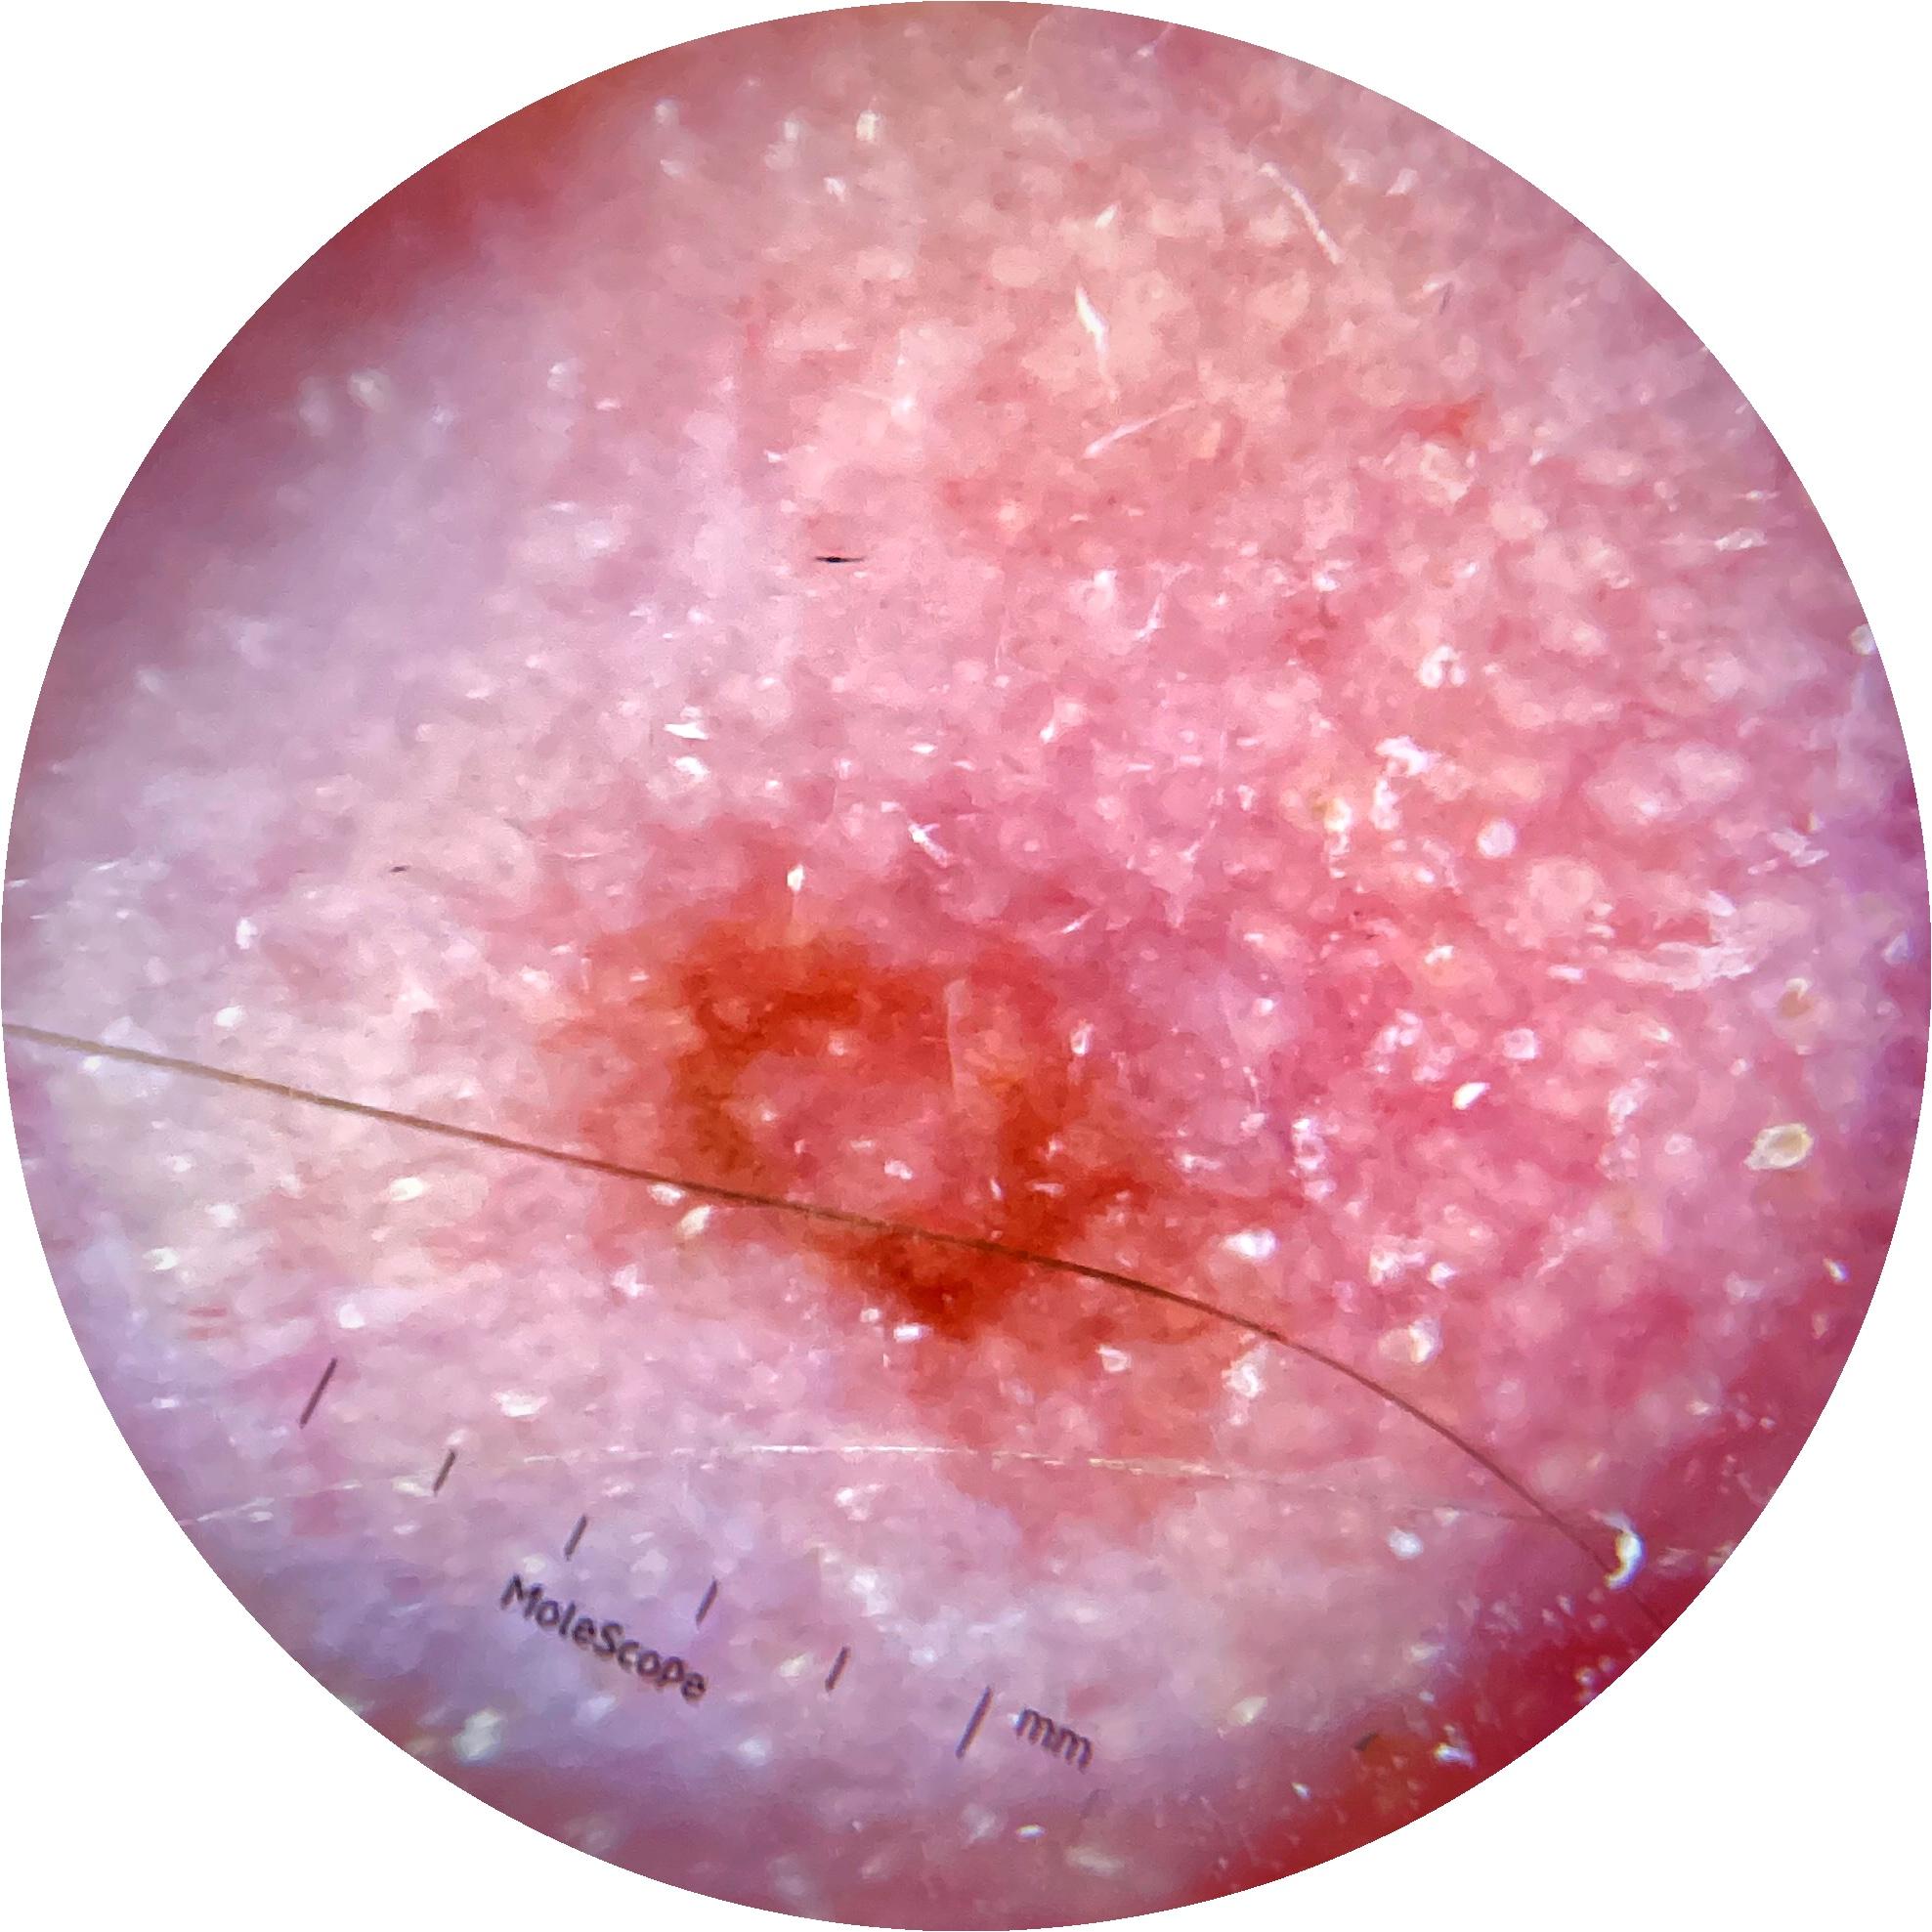

Clinical

Field Value

acquisition_day 148

age_approx 45

anatom_site_1 Head and neck

anatom_site_general head/neck

concomitant_biopsy False

diagnosis_1 Benign

diagnosis_confirm_type single image expert consensus

family_hx_mm True

image_manipulation instrument only

image_type dermoscopic

lesion_id IL_0236417

patient_id IP_8456088

personal_hx_mm True

sex female